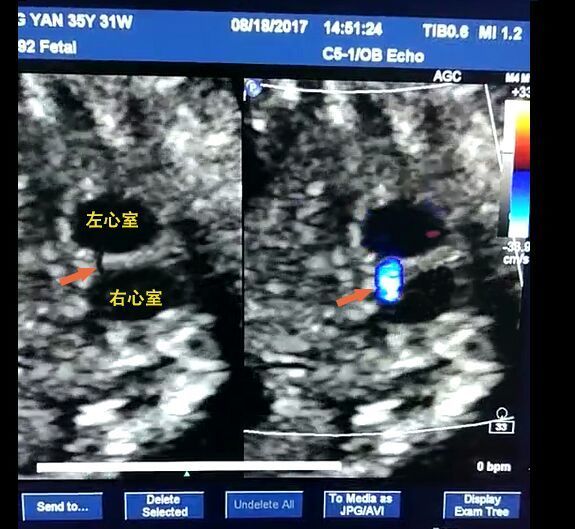

孕24周的四維彩超僅顯示左心室強(qiáng)光點(diǎn),孕婦要求做胎兒心臟進(jìn)一步檢查。圖中彩色血流顯示:兩個(gè)心室之間的異常血流。 【先天性心臟病是較為常見的先天性發(fā)育異常,每1000胎兒中就有6-12個(gè)胎兒心臟異常,隨著二胎放開,高齡產(chǎn)婦增多,胎兒異常的風(fēng)險(xiǎn)更高】